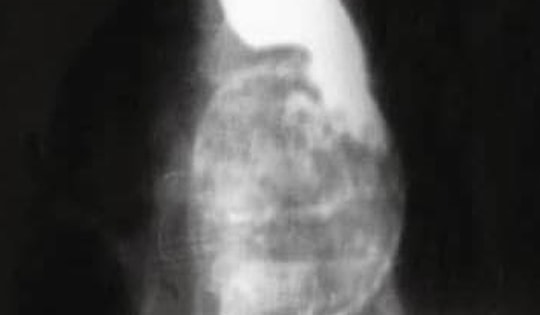

Bé trai đau vùng mắt dữ dội, bác sĩ sốc khi phát hiện dị vật "tàng hình"